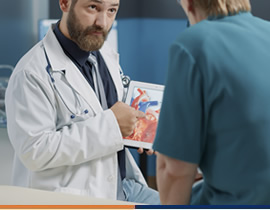

Recupérate de enfermedades que afectan tu sistema cardiovascular

L.E. Irais Marlem Soto Escalante

Recupérate de enfermedades que afectan tu sistema cardiovascular

L.E. Irais Marlem Soto Escalante

La importancia de la rehabilitación cardiopulmonar post covid-19

Francisco Carreto Sulvarán

La importancia de la rehabilitación cardiopulmonar post covid-19

Francisco Carreto Sulvarán

Tomografía como herramienta en diagnóstico de cuadros agudos

Dr. Manuel Peña Hernández

Tomografía como herramienta en diagnóstico de cuadros agudos

Dr. Manuel Peña Hernández